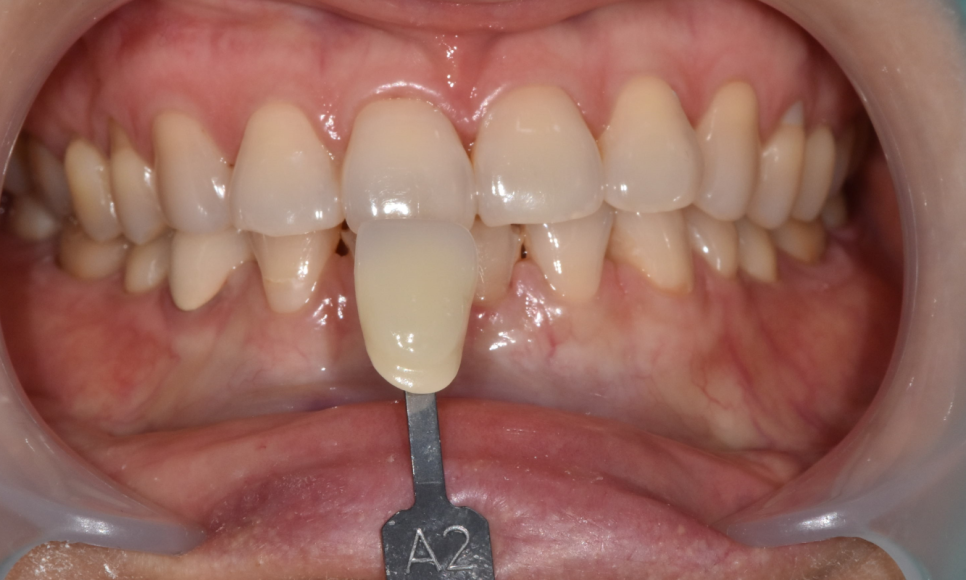

230523

현재 환자분이 가지고 계신 색상은 A2정도입니다.

숫자가 작아질수록 밝아진다 생각하시면 되는데요.

A3 -> A2 -> A1 순서일수록 밝은 것이죠!

앞니는 심미적인 부위라 환자분의 니즈를 파악해보았습니다.